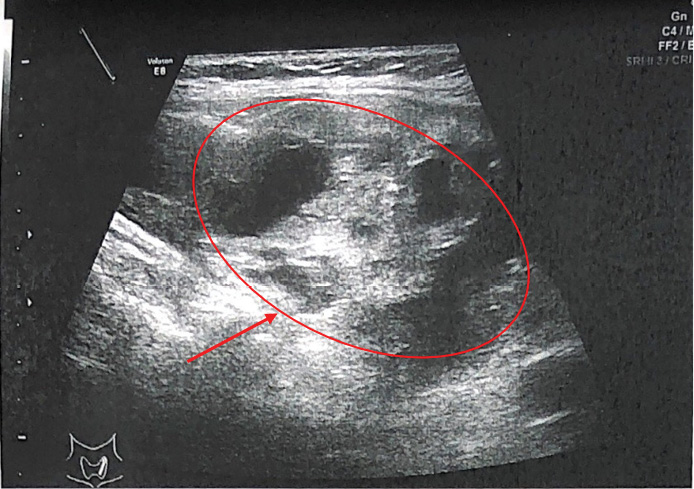

В ходе обследования в ФГБУ «НМИЦ эндокринологии» Минздрава России подтвержден ПГПТ: на фоне гиперкальциемии (Са скорр. на альбумин 2.71 ммоль/л) зафиксировано повышение сывороточной концентрации ПТГ до 1915 пг/мл (15–65), на фоне регулярного приема цинакальцета 60 мг в сутки и длительно некомпенсированного дефицита витамина D (11.8 нг/мл) (табл. 2), а также гипомагниемии (0,64 ммоль/л). Кальциурия не оценивалась ввиду значительного снижения СКФ (до 28 мл/мин/1,73 м²). Проведена топическая диагностика: при УЗИ (рисунок 1) не визуализировано объемное образование околощитовидной железы из-за большого объема конгломерата узлов в левой доле щитовидной железы (European Thyroid Imaging Reporting and Data System — EU-TIRADS 3). Проведена планарная сцинтиграфия с ОФЭКТ/КТ с Tc-99m — Технетрила (MIBI) (рисунок 2), в ходе которой и была определена необычная локализация образования: «левая доля ЩЖ была представлена конгломератным узловым образованием неоднородной структуры, к задней поверхности средней трети левой доли щитовидной железы прилежит образование с четкими ровными контурами овоидной формы гомогенной структуры, размерами 32х37х82 мм, в верхней трети данного образования отмечается гипераккумуляция радиофармпрепарата (РФП); в местах типичного расположения паращитовидных желез дополнительных образований, накапливающих РФП, не определялось. В других областях шеи и верхнего средостения патологического очагового накопления РФП не выявлено.

Рисунок 1. Ультразвуковое исследование щитовидной железы

(стрелкой указан конгломерат узлов).